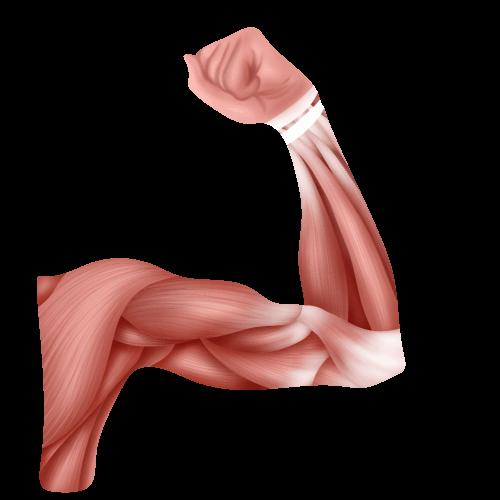

肱二头肌长头腱鞘炎

肱二头肌为屈肘主要肌肉,而长头走形复杂,有长长的腱鞘,容易反复摩擦、脱位等。该部位易产生疼痛,疼痛主要局限为肩前,屈肘疼痛加重。